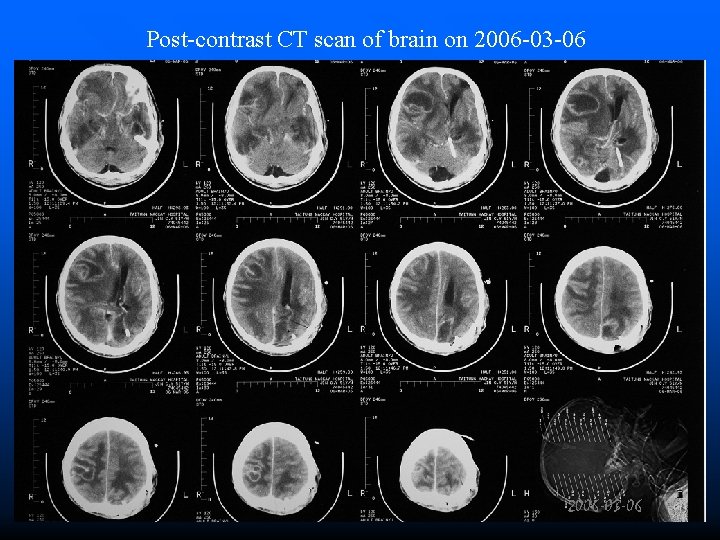

Post-contrast CT scan of brain on 2006 -03 -06

Clinical Course • 2006 -03 -06 ~ 2006 -03 -20 • 2006 -03 -20 • 2006 -03 -21 • 2006 -03 -22 • 2006 -03 -24 Fever off and on Quadriplegia GCS=4~5 WBC=7600 Hb=11. 0 BUN/Cr=12/0. 6 Na/K=144/3. 6 Brain CT Hypotension Passed away